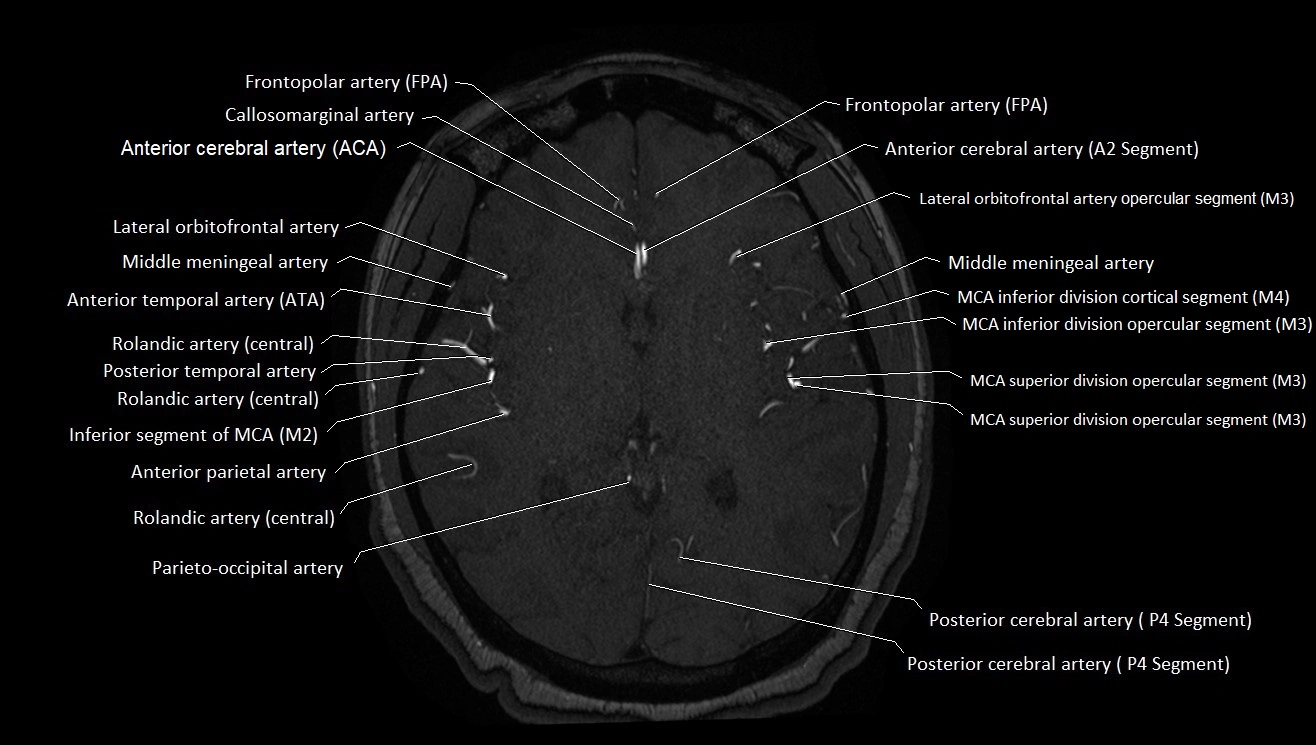

MRI images

image